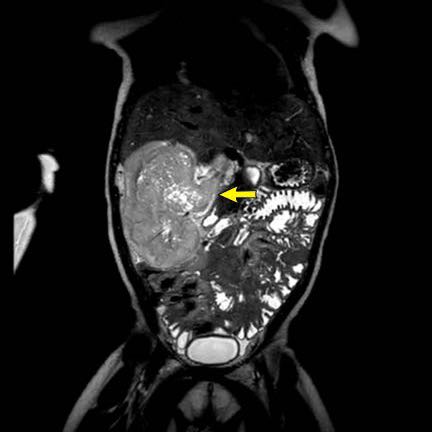

Hình ảnh chuỗi xung T2W mặt phẳng coronal cho thấy một khối u không đồng nhất ở thận trái với các thành phần nang nhỏ.

Khối u ngấm thuốc kém hơn so với phần nhu mô thận bình thường còn lại ở ngoại vi.

Các thành phần đặc của khối u cho thấy hạn chế khuếch tán rõ rệt (mũi tên).

Đây là u Wilms ở bé trai năm tuổi. Hóa trị tiền phẫu được thực hiện theo phác đồ Umbrella của SIOP-RTSG, sau đó tiến hành cắt thận.